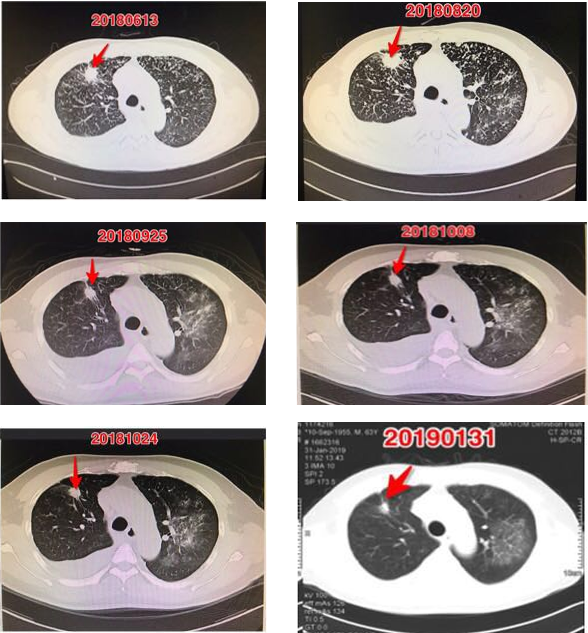

该名已经对小分子靶向药耐药的晚期非小细胞肺腺癌患者存在明显的肿瘤异质性,TME表现出免疫抑制性特点。针对这些特点,采取针对3个靶抗原(靶点)的ACTL替换治疗,取得明显疗效。